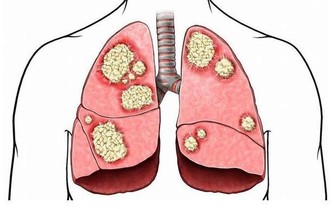

體內濕氣重的人,是健康的隱憂,一旦與外來的濕氣裡外相合,就更加糾纏不清了,這也是濕氣重的人一遇到陰雨天或梅雨季節,濕濁阻遏氣機與清陽,時常會覺得頭昏沉、提不起勁、很想睡覺、四肢沉重無力、大便變的軟黏的排不乾淨、胃口不好、嘴巴淡淡的沒什麼味覺,甚至皮膚濕疹發作或搔癢加重…從中醫的觀點來看,水腫病與肺、脾、腎三臟關係最大,身體的水分代謝是透過肺的通調水道、脾的運化轉輸和腎的溫化蒸動等生理功能協調下完成,而中醫在治療水腫原則,有「腰以上腫發汗腰以下腫利小便」一說,再搭配不同病因病機去調理。